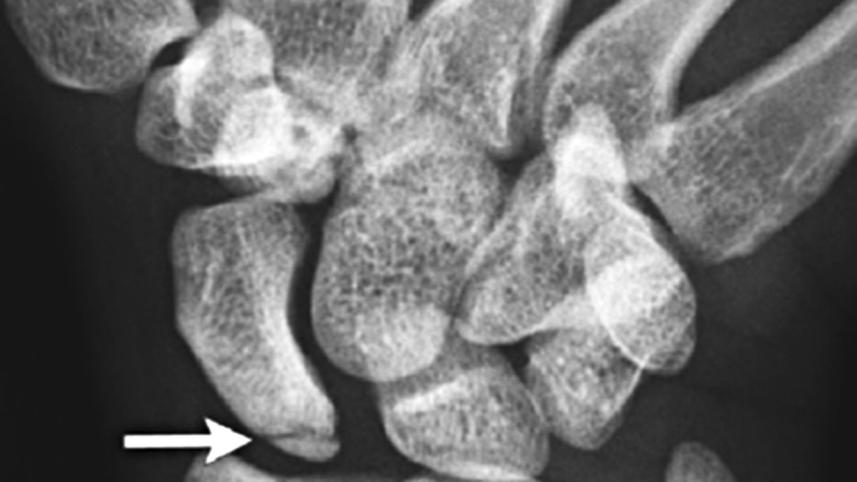

Missed fractures are a common category of diagnostic errors and can cause malunion, osteonecrosis, and arthritis, with consequent impairment of function. In a study, researchers examined 135,845 x-rays of various bones (nearly 35,000 of which involved the wrist). Senior orthopaedic surgeons scored each image for the presence of fractures and used neural network artificial intelligence (AI) techniques to 'train' a computer to diagnose wrist fractures.

Researchers then conducted a controlled experiment with 40 emergency department clinicians: Each participant was shown an x-ray and asked to determine the presence or absence of a fracture. Then, those in a randomly assigned 'aided' group were shown the computer model's fracture assessment and asked again to determine the presence or absence of a fracture. When aided performance versus unaided performance were compared in a series of 300 x-rays, sensitivity for diagnosing fracture was 92% versus 81%, and specificity was 94% versus 88%.